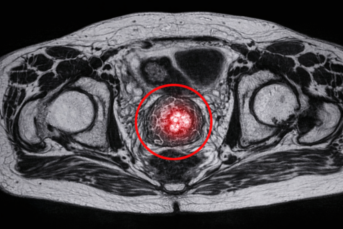

3. Bildgebung: Meist eine spezielle Magnetresonanztomographie (MRT) der Prostata.

4. Prostatabiopsie: Entnahme von Gewebeproben zur Sicherung der Diagnose.